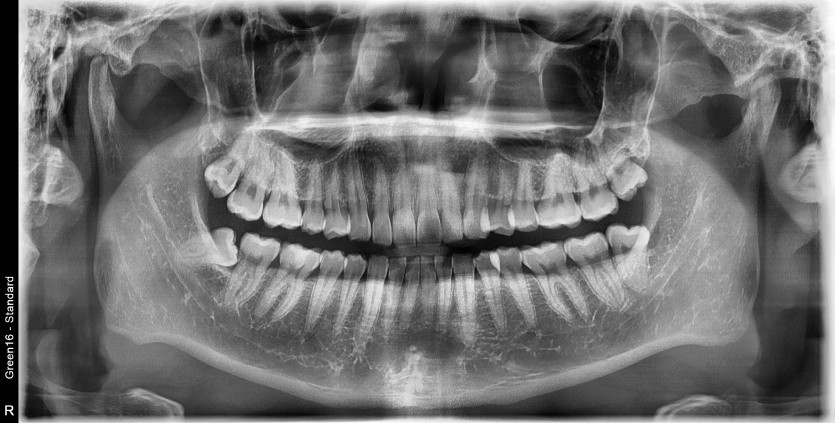

#18,48 사랑니 발치

구강 외과 전문의가 당일 발치했습니다.